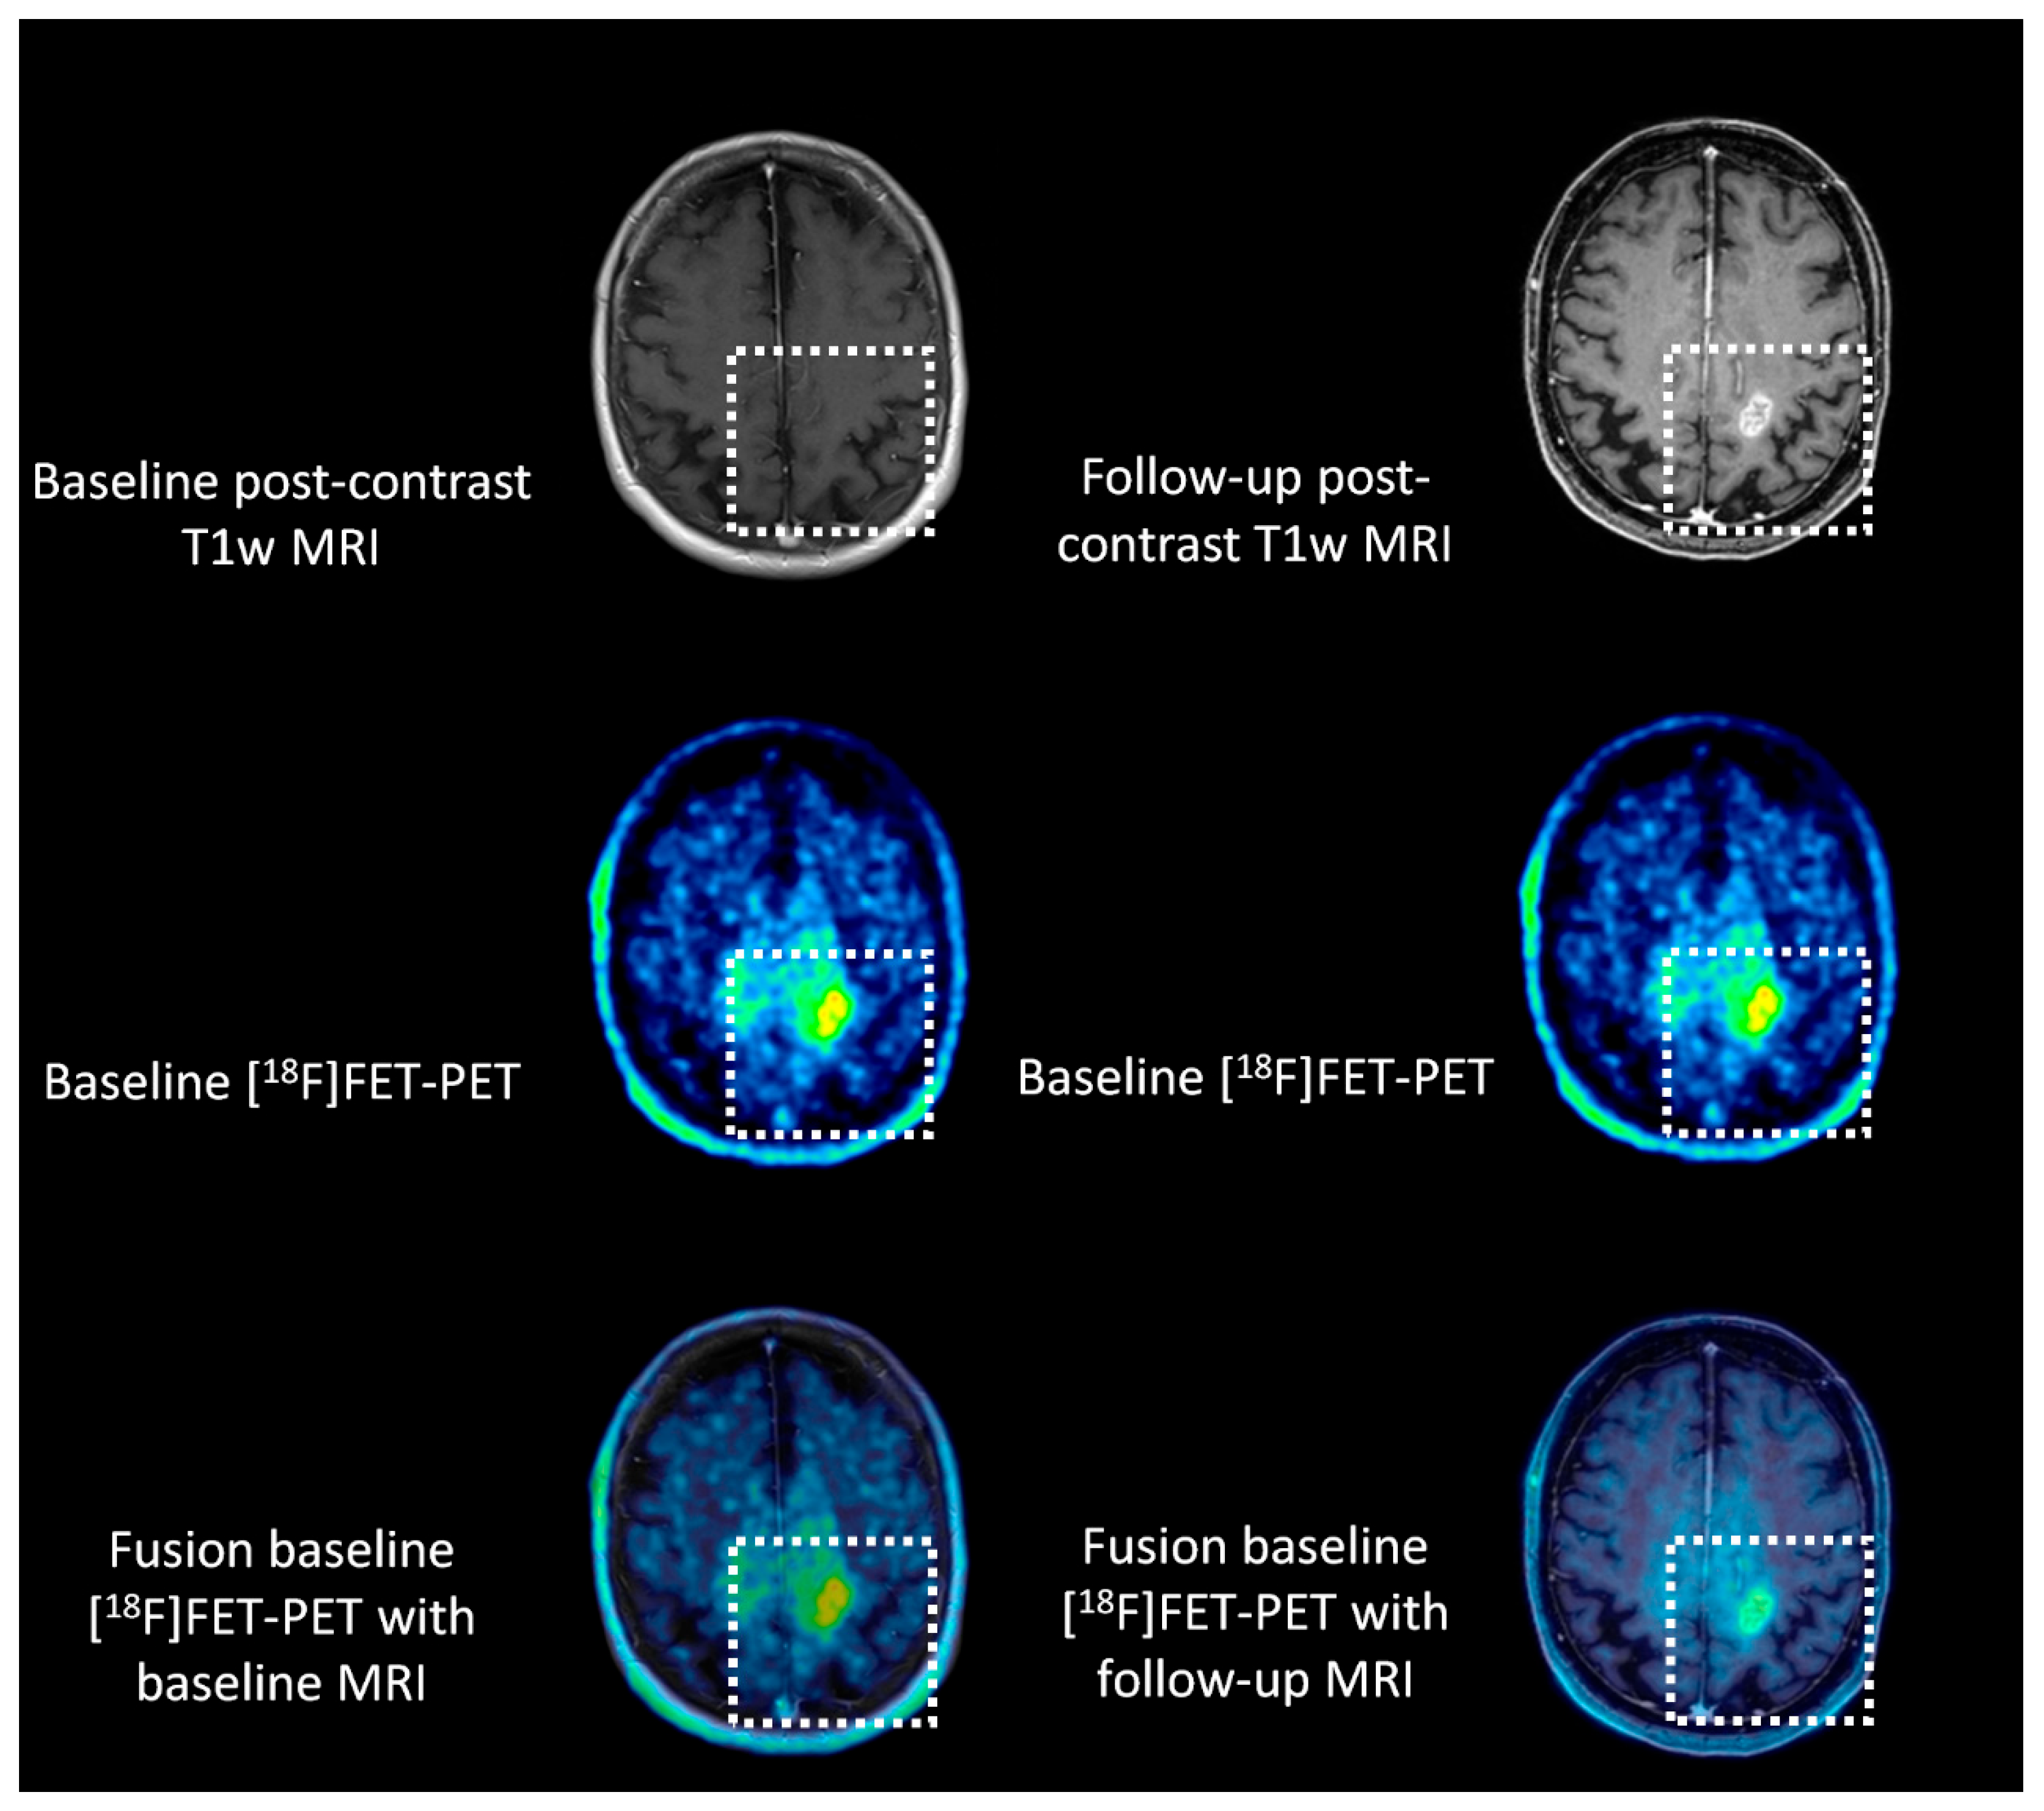

2.4. Co-Registration of Different Imaging Modalities at Different Time Points